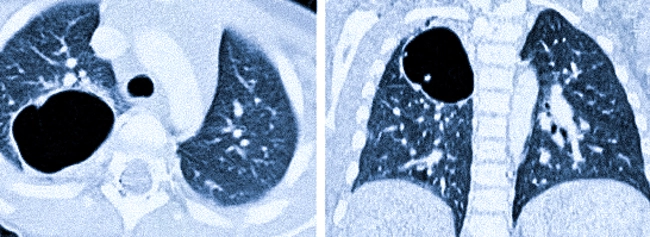

На компьютерной томографии можно наблюдать следующие особенности:

- одиночное замкнутое образование, представленное в виде кольцевидной тени округлой формы с четкими стенками (если нет воспалительного процесса, толщина стенки не превышает 2-3 мм);

- обычно располагается поблизости от главных дыхательных путей;

- внутреннее содержимое может быть Представлено белковой жидкостью, кровью, кальциевой взвесью или воздухом.

На рентгеновских снимках и КТ можно наблюдать объемное бронхогенное образование у новорожденного (стрелки указывают на патологию).